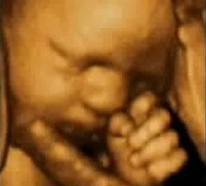

Feto cara cara2 Feto Oreja manos carita bebe Barret Barrett1 Pólipo Diverticulos Cancer rectal Transverso Duodeno Rayos%20x.jpg